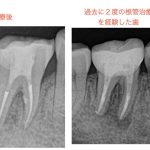

繰り返す根管治療、行き着く果ては歯根破折で抜歯

歯を失う原因のうちの一つ垂直性歯根破折(根のひび…